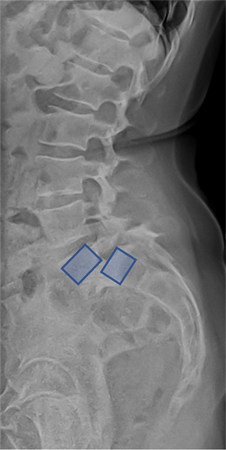

Spondylolisthesis

Spondylolisthesis is a spinal condition where one vertebra (a bone in the spine) slips forward in relation to the one below it.

Forward displacement is called anterolisthesis and backwards is termed retrolisthesis.

Spondylolysis is a spinal condition that occurs when a fracture or defect develops in one of the vertebrae in the spine, most commonly in the lower back (lumbar spine). When the defect leads to shifting out of position, it is termed spondylolisthesis.